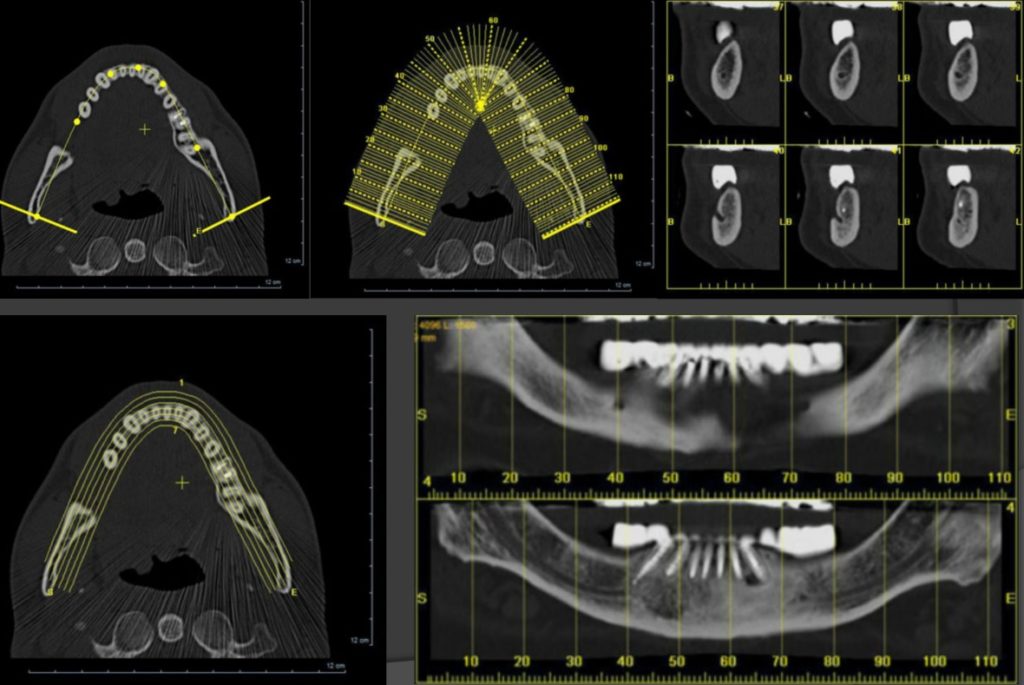

Technologie 3D (tomographie volumique à faisceau conique) pour des images très précises des dents et de l'os. Indispensable pour l'implantologie et la chirurgie.

Production d'images en trois dimensions, souvent utilisé pour la visualisation des structures osseuses, le diagnostic de fractures ou infections et la planification d'implants.